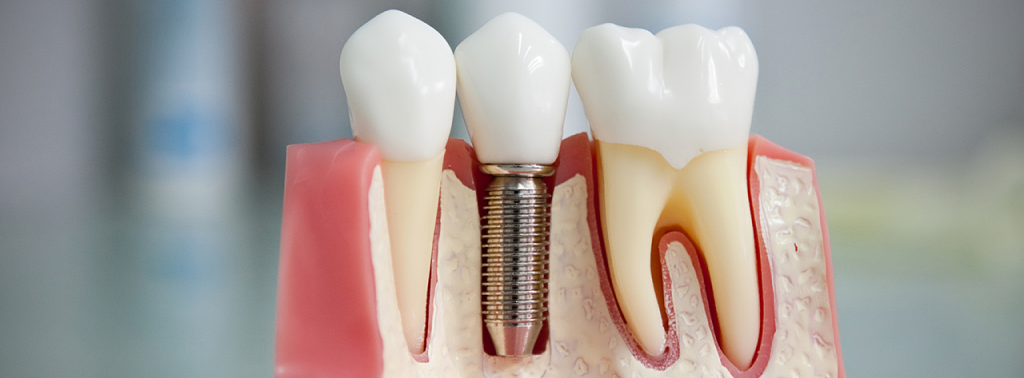

Це спосіб штучного заміщення втрачених зубів. Зубні імплантати виготовлені з титану, що має абсолютну біосумісність з тканинами організму. Хірургічним шляхом вони встановлюються на місце видалених коренів зубів і надалі є опорою для незнімних або умовно-знімних протезів, а також для кращої фіксації знімних протезів.

• Отримання конструкції імплантат-коронка, максимально наближеної до фізіології зуба